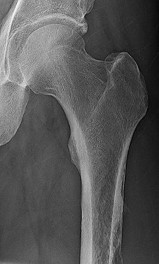

This patient has a dedifferentiated liposarcoma within a preexisting atypical lipomatous tumor. The imaging demonstrates a large fatty mass with increased internal septations proximally (the atypical lipomatous tumor) and a solid enhancing mass distally (the dedifferentiated portion). A biopsy reveals a high-grade liposarcoma. The other diagnostic responses do not reflect sarcomatous transformation of the lesion.

Surgical treatment of a high-grade sarcoma involves wide surgical resection. Radiation decreases local recurrence but does not clearly influence overall survival. The role of chemotherapy in high-grade soft-tissue sarcomas remains investigational; there is a modest (8%-15%) associated improvement in overall survival.

Intramuscular lipomas and atypical lipomatous tumors are treated with marginal resection alone. Radiation therapy for soft-tissue sarcomas may be given before or after surgery. When administered before surgery, patients have a higher wound complication rate but better long-term function attributable to lower rates of lymphedema, fibrosis, and contractures.